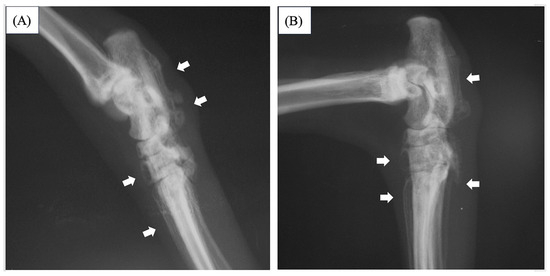

2. Case Description